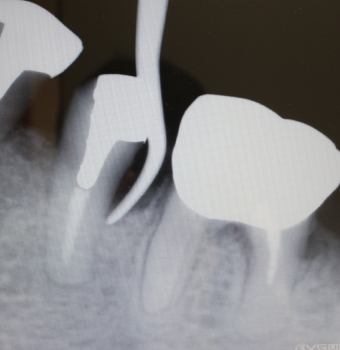

同部のX-ray

骨補填剤充填後のX-ray

2016年07月21日撮影

術後約3.5カ月後

予後良好